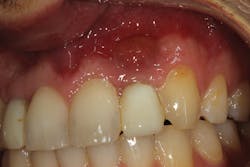

Because of this alveolar resorptive pattern after tooth extraction, bone grafting the extraction socket after tooth extraction procedures has become a solution that attempts to limit the amount of hard- and soft-tissue loss. There are many systematic reviews in the literature that compare the results of residual ridge dimension following tooth extraction after the use of a bone graft (with or without a membrane) versus extraction alone without grafting.7

Indications for bone grafting extraction sites include:

• site development to increase hard and soft tissue for pontic sites in fixed bridge prosthetics (figures 9–14);• correcting bone defects impinging upon anatomical structures after tooth extraction, such as oroantral communication (figure 18); and

• preserving tissue structure for subsequent dental implant therapy.Decision matrix